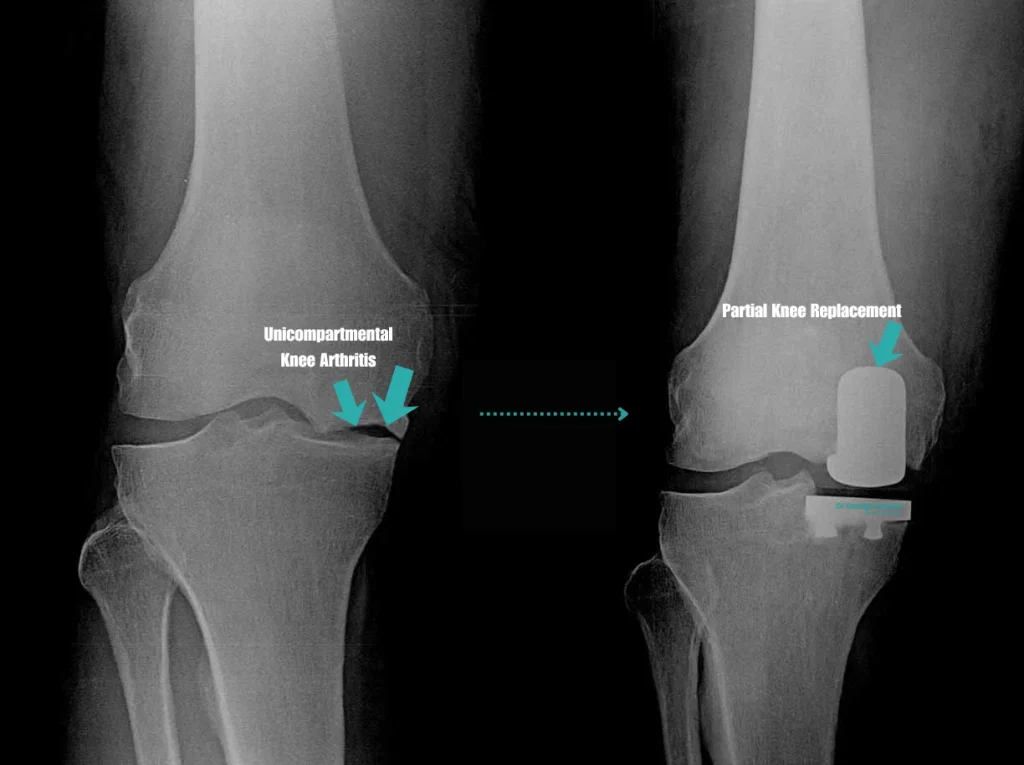

• Partial Knee Replacement Surgery

Partial Knee Replacement